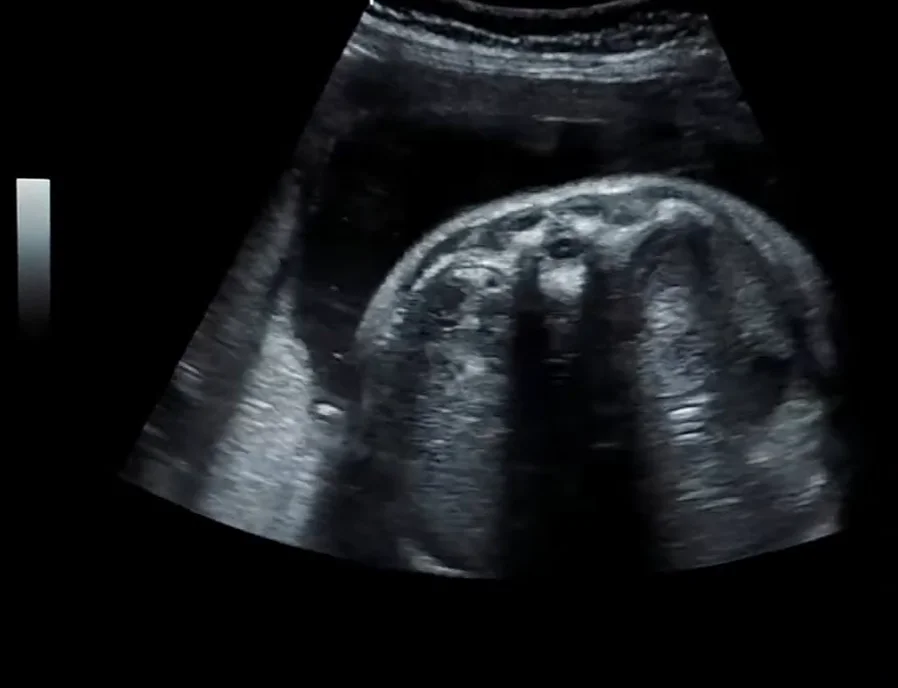

• Các biến thể phát triển của thận

• Bất sản thận một bên (Unilateral Renal Agenesis)

• Thận đôi - niệu quản đôi (Duplicated Collecting System)

• Thận lạc chỗ vùng chậu thai nhi (Pelvic Kidney)

• Thận móng ngựa thai nhi (Horseshoe Kidney)

• Thận lạc chỗ bắt chéo dính nhau ở thai (Crossed fused renal ectopia)

• Thận loạn sản đa nang thai nhi (Multicystic Dysplastic Kidney - MCDK)

• Thận đa nang di truyền lặn thai nhi (Autosomal Recessive Polycystic Kidney Disease - ARPKD)